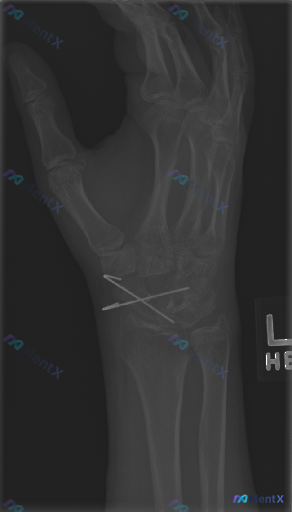

整理到一份左腕关节正位X光的影像资料,先把客观表现梳理一下: 1. 内固定与骨结构:腕部可见两枚交叉克氏针,穿过舟骨及部分近排腕骨区域;舟骨区域有明确的骨折线透亮影、骨皮质不连续,呈陈旧性骨折或不愈合表现;桡骨远端、尺骨及其他腕骨未见明确新发骨折线。 2. 腕骨排列与对位:受内固定和陈旧骨折影响,舟...